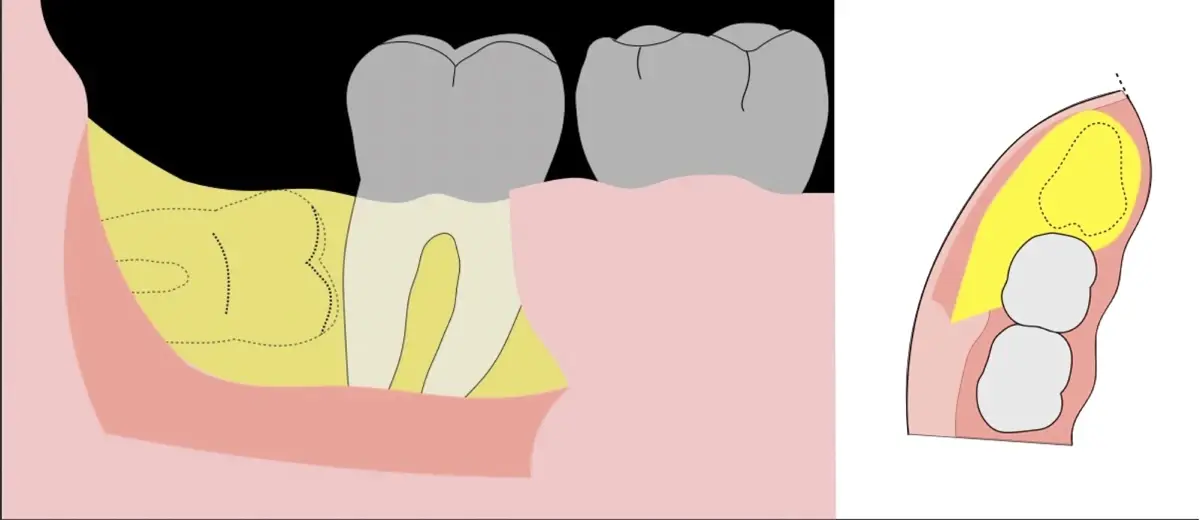

Para realizar la técnica de extracción de una tercera molar, una vez que se ha confirmado su diagnóstico, se debe considerar la posición del diente (vertical, mesioangular, distoangular, horizontal u otras), profundidad y grado de impacto, obstrucción a la erupción asociada a la segunda molar, morfología de la raíz (la curvatura de las raíces controla el camino de la exodoncia), relación con el canal del conducto dentario inferior, la patología asociada, la densidad ósea y la Integridad de la segunda molar.

Es imprescindible conocer la ubicación de la tercera molar. Se puede emplear, adicionalmente a la evaluación clínica, herramientas radiográficas (panorámica y periapical) y tomográficas (Cone beam) para determinar la posición, grado de retención y proximidad a estructuras vecinas de riesgo como el nervio dentario inferior y así evitar lesiones (Figura 1).

El procedimiento se inicia colocando anestesia troncular para bloqueo del nervio dentario inferior y sus ramas. Luego, se establecerá el diseño de acceso según la disposición de la molar a extraer. Para fines didácticos, se explicará cómo se realizaría la extracción de la molar de la Figura 1: se realiza una incisión horizontal a nivel de la zona retromolar hasta llegar a distal de la segunda molar, continuándose con una incisión intrasurcular hasta mesial de la segunda molar, finalizando con una incisión vertical a espesor total hasta llegar a la línea mucogingival (Figura 2).